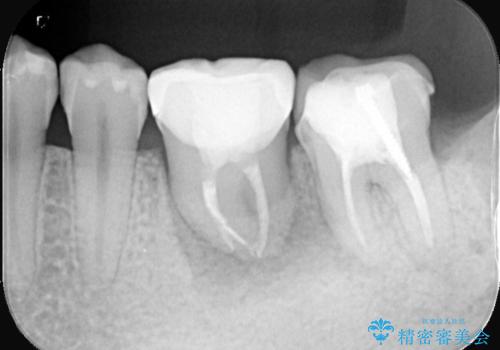

左下6番目の歯の周りに大きく透過像を認め、再根管治療後の予後が良くない可能性が大きく当院でも抜歯適用歯と説明しました。欠損部に対しインプラント治療や歯牙移植(左下の親知らずの移植)、ブリッジを提案し、歯牙移植を行うこととなりました。

保存が難しい左下6番目の歯を抜歯し、左下8番目の歯(親知らず)を抜歯窩に移植しました。歯牙移植後の動揺防止のため暫間固定を行っています。